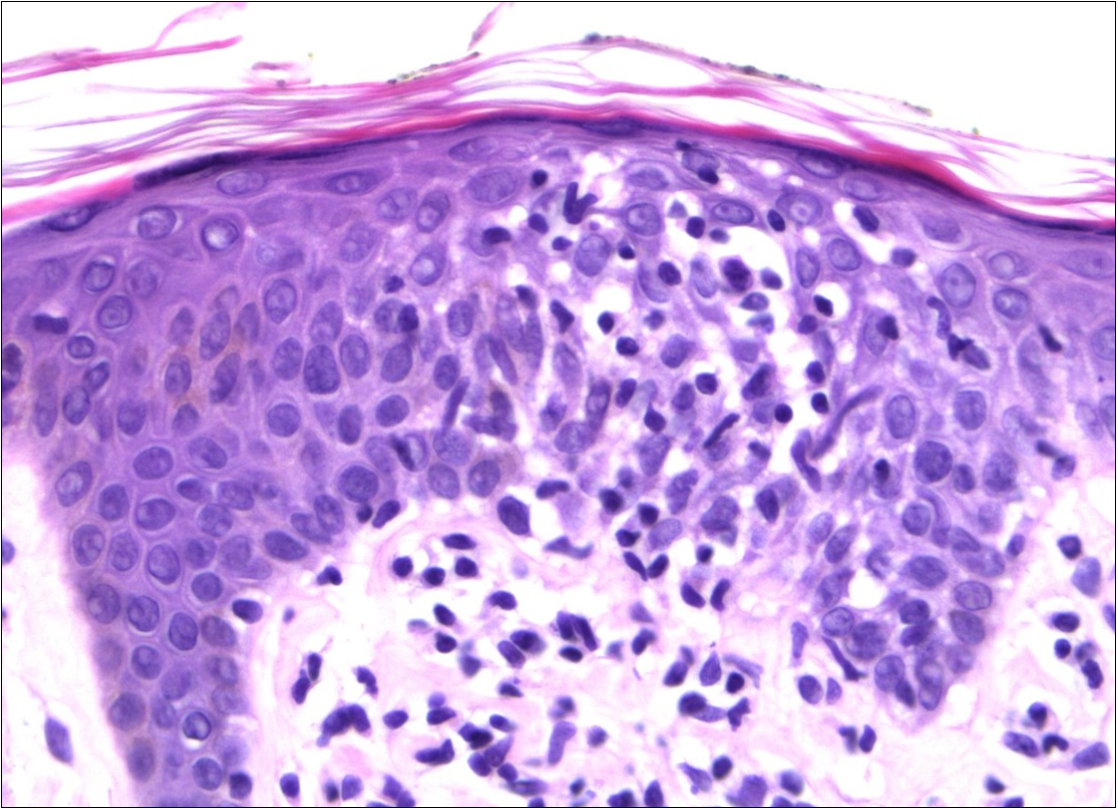

A skin biopsy revealed a dense pleomorphic lymphoid infiltrate in the superficial dermis (Figure 3) and epidermotropism. Immunohistochemistry showed a T-cell phenotype, positive for CD3, CD4, CD5 and negative for CD20.

Figure 3.The skin biopsy revealed a dense pleomorphic lymphoid infiltrate in the superficial dermis and epidermotropism (HEx40)